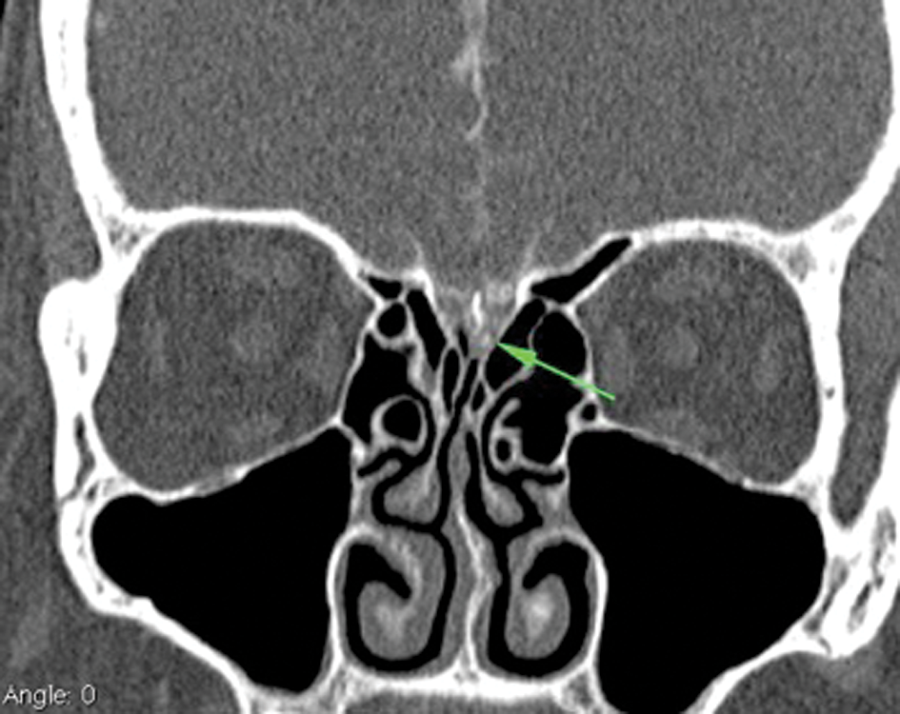

Cerebrospinal fluid (CSF) rhinorrhoea not infrequently presents to the ENT surgeon. Attention should be directed clinically and radiologically to the anterior skull base. The cause of the CSF rhinorrhoea, if active, may be interrogated using CT cisternography. In this technique, contrast medium is injected into the CSF, typically of the lumbar thecal sac through a lumbar puncture. High resolution CT imaging of the anterior and central skull base is then performed to identify a potential site of CSF leak. Multislice CT has greatly enhanced the radiological assessment of the anterior skull base through its improved resolution and improved high resolution multiplanar reformatting capabilities (Figure 1).

Figure 1: CT cisternography of a patient with active CSF rhinorrhoea: coronal reformatted image from multislice axial CT volume acquisition. The high density contrast medium within the CSF subarachnoid spaces of the subfrontal brain parenchyma and the anterior interhemispheric fissure can be seen. The anterior skull base defect in the left mid-cribriform plate with associated contrast extension identifies the site of the CSF leak (arrow). This was successfully closed endoscopically.